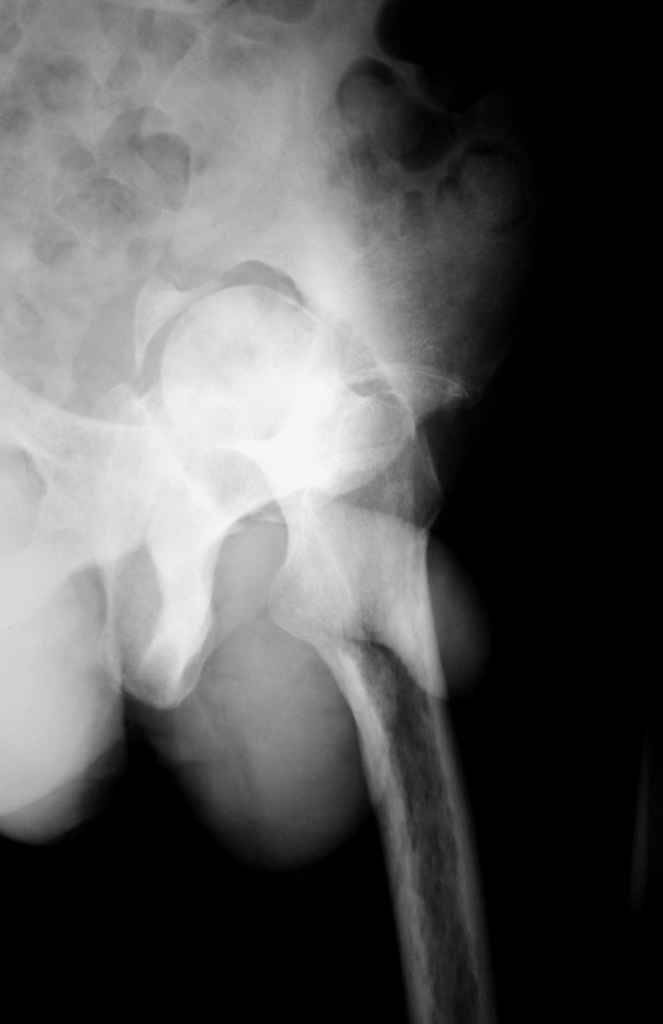

К нам обратился житель Казахстана с застарелым вывихом бедра. Травма год назад, вместо синтеза заднего края казахскими умельцами установлена клинковая пластина, через 6 мес удалена. Больной ходит с тростью,сгибание в т-б 90, разгибание 170, укорочение 5 см, боли не выражены, анальгетиками не пользуется. Настроен на эндопротезирование в клинике, где есть опыт подобных операций (возможно за рубежом).Наш план: аппарат таз-бедро, постепенное низведение бедра, "октопус" с пластикой. Но с такими большими дефектами мы не сталкивались.Есть вариант сначала аппарат, затем реконструкция впадины, протез обычный через 4-6 мес.Есть мнение не восстанавливать длину. Будем признательны за полезные советы. Было бы интересно посмотреть пример.

Прилагаю в качестве иллюстрации одну из последних операций.

Еще одно наблюдение, неправильно сросшийся перелом заднего отдела ВВ с ввихом головки бедра 16-и летней давности.